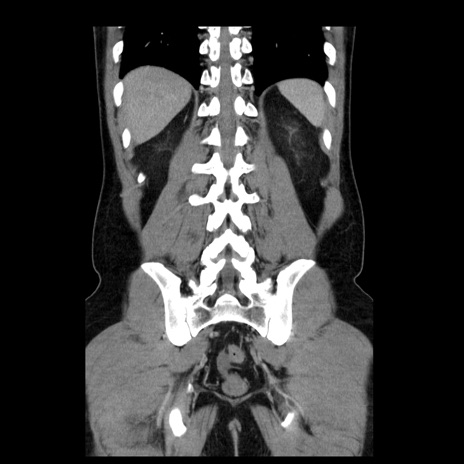

横断像

【症例】30歳代男性

【主訴】腹痛、嘔吐

【現病歴】昨晩から突然の腹痛あり、その後嘔吐、軟便も出現。腹痛が改善しないため救急搬送となる。2日前にしめ鯖の食事歴あり。

【身体所見】意識清明、苦悶様、BP 135/90mmHg、BT 35.7℃、腹部:平坦、やや硬、心窩部〜臍部に自発痛、圧痛あり、筋性防御+、反跳痛-

【データ】WBC 8100、CRP 0.57